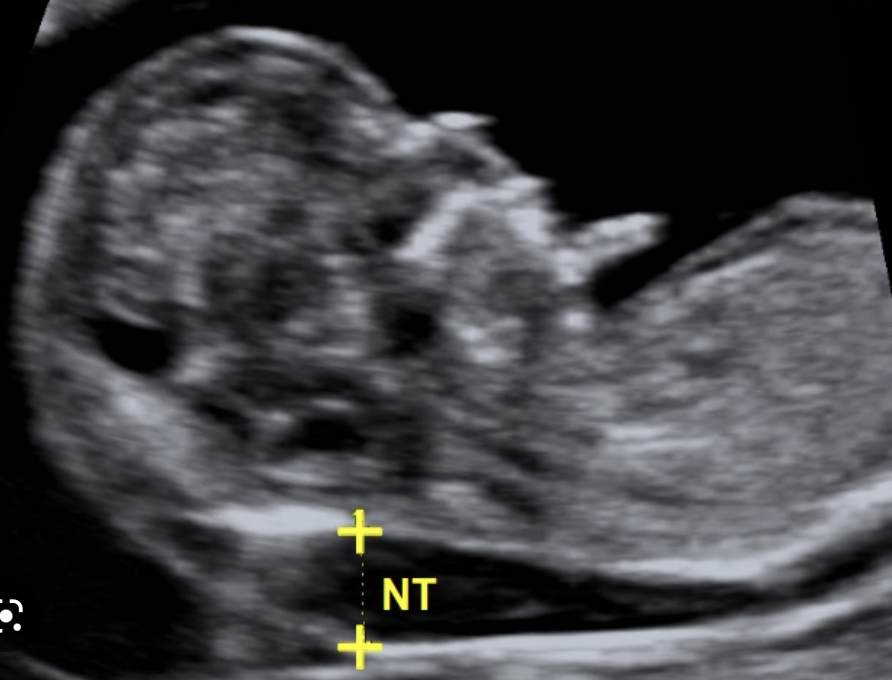

What is the role of USS in the combined test?

• it measures the nuchal translucency

• this is the thickness of the back of the neck of the foetus

• Down’s syndrome causes nuchal thickness > 6mm